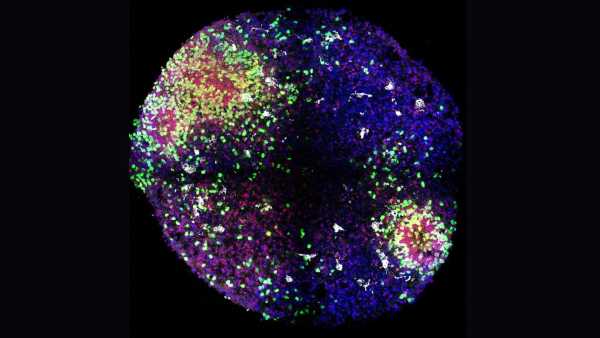

Відомо, що у людей з розсіяним склерозом (РС) високий рівень імунних клітин, які називаються цитотоксичними Т-клітинами, що зазвичай допомагають знищувати ракові та інфіковані мікробами клітини. Однак при РС ці клітини накопичуються в ділянках з видимим пошкодженням мієліну, але роль, яку ці клітини відіграють у цьому захворюванні, досі залишалася значною мірою загадкою.

У дослідженні, опублікованому 27 вересня в журналі Science Immunology, вчені вивчили Т-клітини 12 пар однакових близнюків. У кожній парі один близнюк мав розсіяний склероз, а інший – ні. Коли один близнюк хворіє на розсіяний склероз, другий має приблизно 1 до 4 шансів захворіти на це захворювання в майбутньому. Таким чином, Т-клітини другого близнюка дають уявлення про імунну систему людей, які, ймовірно, зрештою переживуть повноцінний розсіяний склероз.

Дослідники досліджували гени, які були активовані в Т-клітинах близнюків, вимірюючи РНК, молекулу, яка допомагає клітинам виробляти білки з ДНК-планів. Аналіз показав, що Т-клітини людей з розсіяним склерозом або запаленням ЦНС були активнішими та запускали більше імунної сигналізації, ніж у людей без жодного з цих захворювань. Коротше кажучи, ці Т-клітини здавалися особливо реактивними. Дослідники також виявили більшу активацію в генах, які допомагають підтримувати Т-клітини увімкненими.

Чим раніше ми втрутимося в процес запалення та руйнування нервової системи, тим більший вплив ми матимемо.

Доктор Девід Дункан, Hackensack Meridian Health

Загалом, чим на більшій стадії захворювання була людина, тим більше у неї було Т-клітин, які демонстрували ці генетичні зміни. Це підтверджує гіпотезу про те, що ці Т-клітини викликають запалення при розсіяному склерозі.